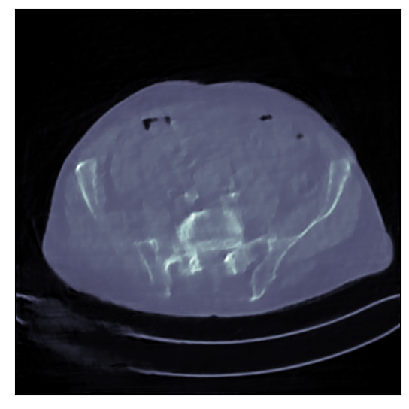

We consider the variational reconstruction framework for inverse problems and propose to learn a data-adaptive input-convex neural network (ICNN) as the regularization functional. The ICNN-based convex regularizer is trained adversarially to discern ground-truth images from unregularized reconstructions. Convexity of the regularizer is desirable since (i) one can establish analytical convergence guarantees for the corresponding variational reconstruction problem and (ii) devise efficient and provable algorithms for reconstruction. In particular, we show that the optimal solution to the variational problem converges to the ground-truth if the penalty parameter decays sub-linearly with respect to the norm of the noise. Further, we prove the existence of a sub-gradient-based algorithm that leads to a monotonically decreasing error in the parameter space with iterations. To demonstrate the performance of our approach for solving inverse problems, we consider the tasks of deblurring natural images and reconstructing images in computed tomography (CT), and show that the proposed convex regularizer is at least competitive with and sometimes superior to state-of-the-art data-driven techniques for inverse problems.